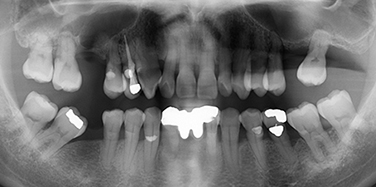

Step 1 – Diagnosis by Brener Clinic

Treatment Planning, including 3d Cone Beam Scans

Your All-on-4 treatment begins with a  consultation at Brener Clinic. At this time Brener Clinic will examine your mouth and teeth to determine your suitability for the All-on-4 implant treatment. We take 3D Cone Beam CT Scans to assist with treatment planning. Using Digital Smile Design (DSD) technology, we collect other records, such as facial photographs and videos, as well as digital impressions of your upper and lower jaws. A thorough medical history is taken so we can communicate with your doctor and specialist medical team if necessary. This information allows us to clinically analyse your treatment options, digitally design your smile and plan your All-on-4 surgery.